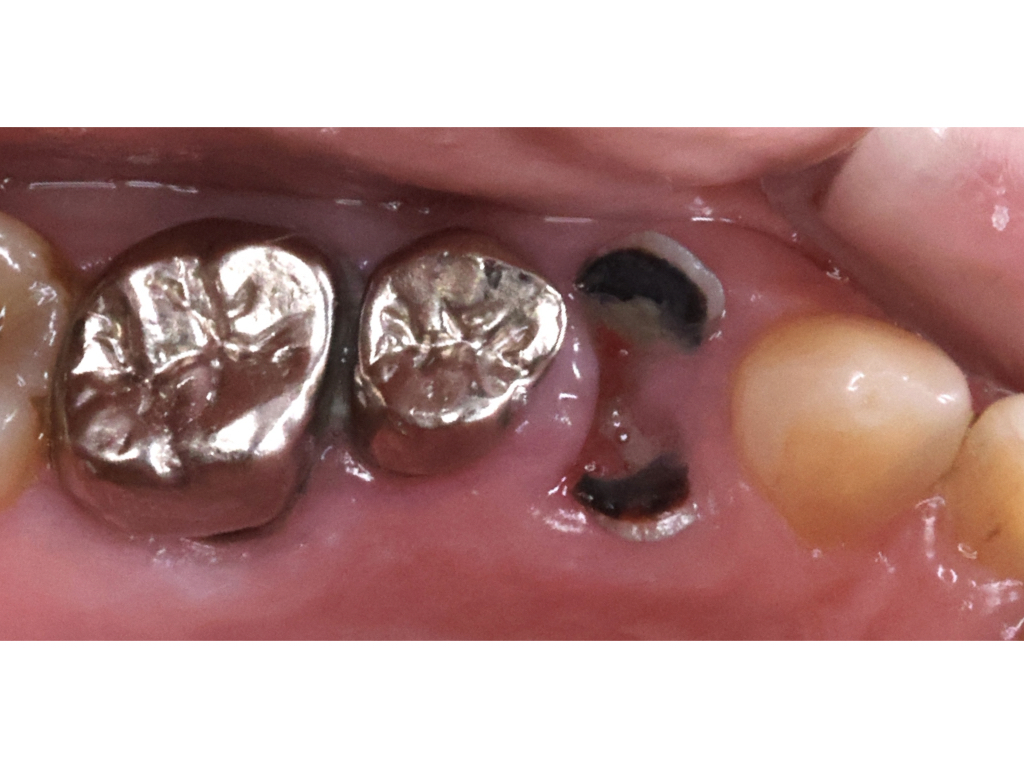

症例 ブリッジ治療

| 主訴 | 歯のない部分を治したい |

| 治療内容 | メタルセラミッククラウンブリッジ |

| リスク・副作用 | 治療後に知覚過敏が起こる可能性があります。土台となる歯に負荷がかかるため歯が破折するリスクがあります。 |